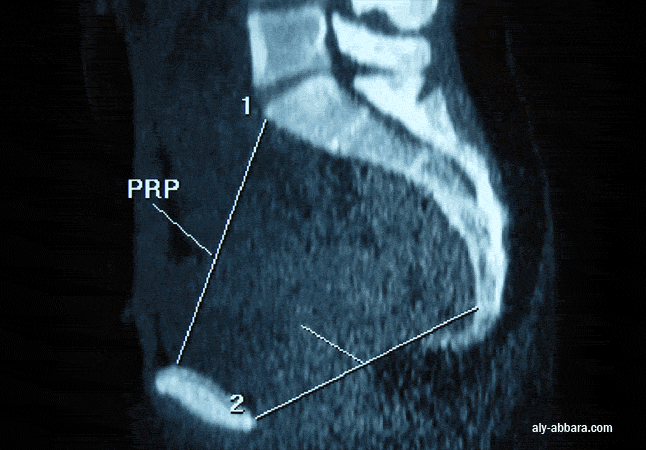

Bassin féminin en coupe sagittale médiane : Diamètre sous-sacro-sous-pubien (SSSP) mesuré de la pointe inférieure de la dernière pièce sacrée au bord inférieur du pubis. Il représente le diamètre antéro-postérieur utile du dégagement au niveau du détroit inférieur. ; en moyenne 95 mm.